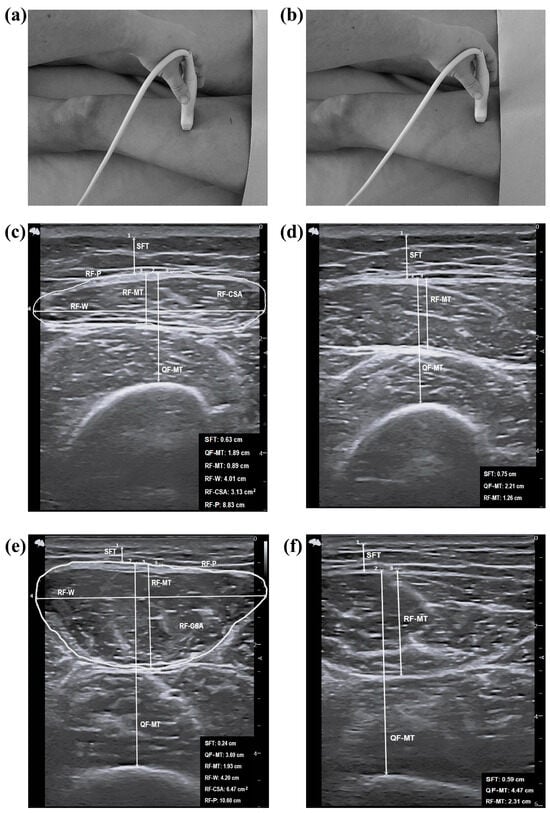

2.5. Assessment of Ultrasound Parameters

| SFT (cm) | All | 1.28 ± 0.57 | 0.80 ± 0.39 | 0.004 | <0.001 | 0.221 |

| QF-MT (cm) | All | 2.31 (0.89) | 2.81 (1.35) | 0.058 | <0.001 | 0.316 |

| RF-MT (cm) | All | 1.32 (0.45) | 1.33 (0.82) | 0.205 | <0.001 | 0.377 |

| RF-W (cm) | All | 3.89 ± 0.38 | 4.05 ± 0.22 | 0.109 | <0.001 | 0.345 |

| RF-CSA (cm2) | All | 4.06 (1.60) | 4.67 (3.10) | 0.085 | <0.001 | 0.333 |

| RF-P (cm) | All | 8.97 (0.92) | 9.75 (1.69) | 0.014 | <0.001 | 0.261 |

| SFT (cm) | All | 1.45 ± 0.59 | 1.08 ± 0.47 | 0.061 | <0.001 | 0.319 |

| QF-MT (cm) | All | 3.29 ± 0.71 | 3.80 ± 1.14 | 0.264 | <0.001 | 0.392 |

| RF-MT (cm) | All | 1.64 (0.33) | 1.93 (0.95) | 0.114 | <0.001 | 0.347 |